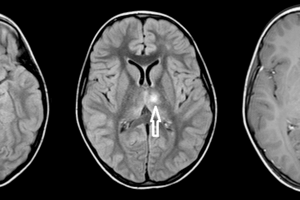

Dawson's fingers of MS

Multiple Sclerosis

MULTIPLE SCLEROSIS is aptly named for the scleroses (scars or plaques) that occur as the disease resurfaces in multiple episodes. Read more »